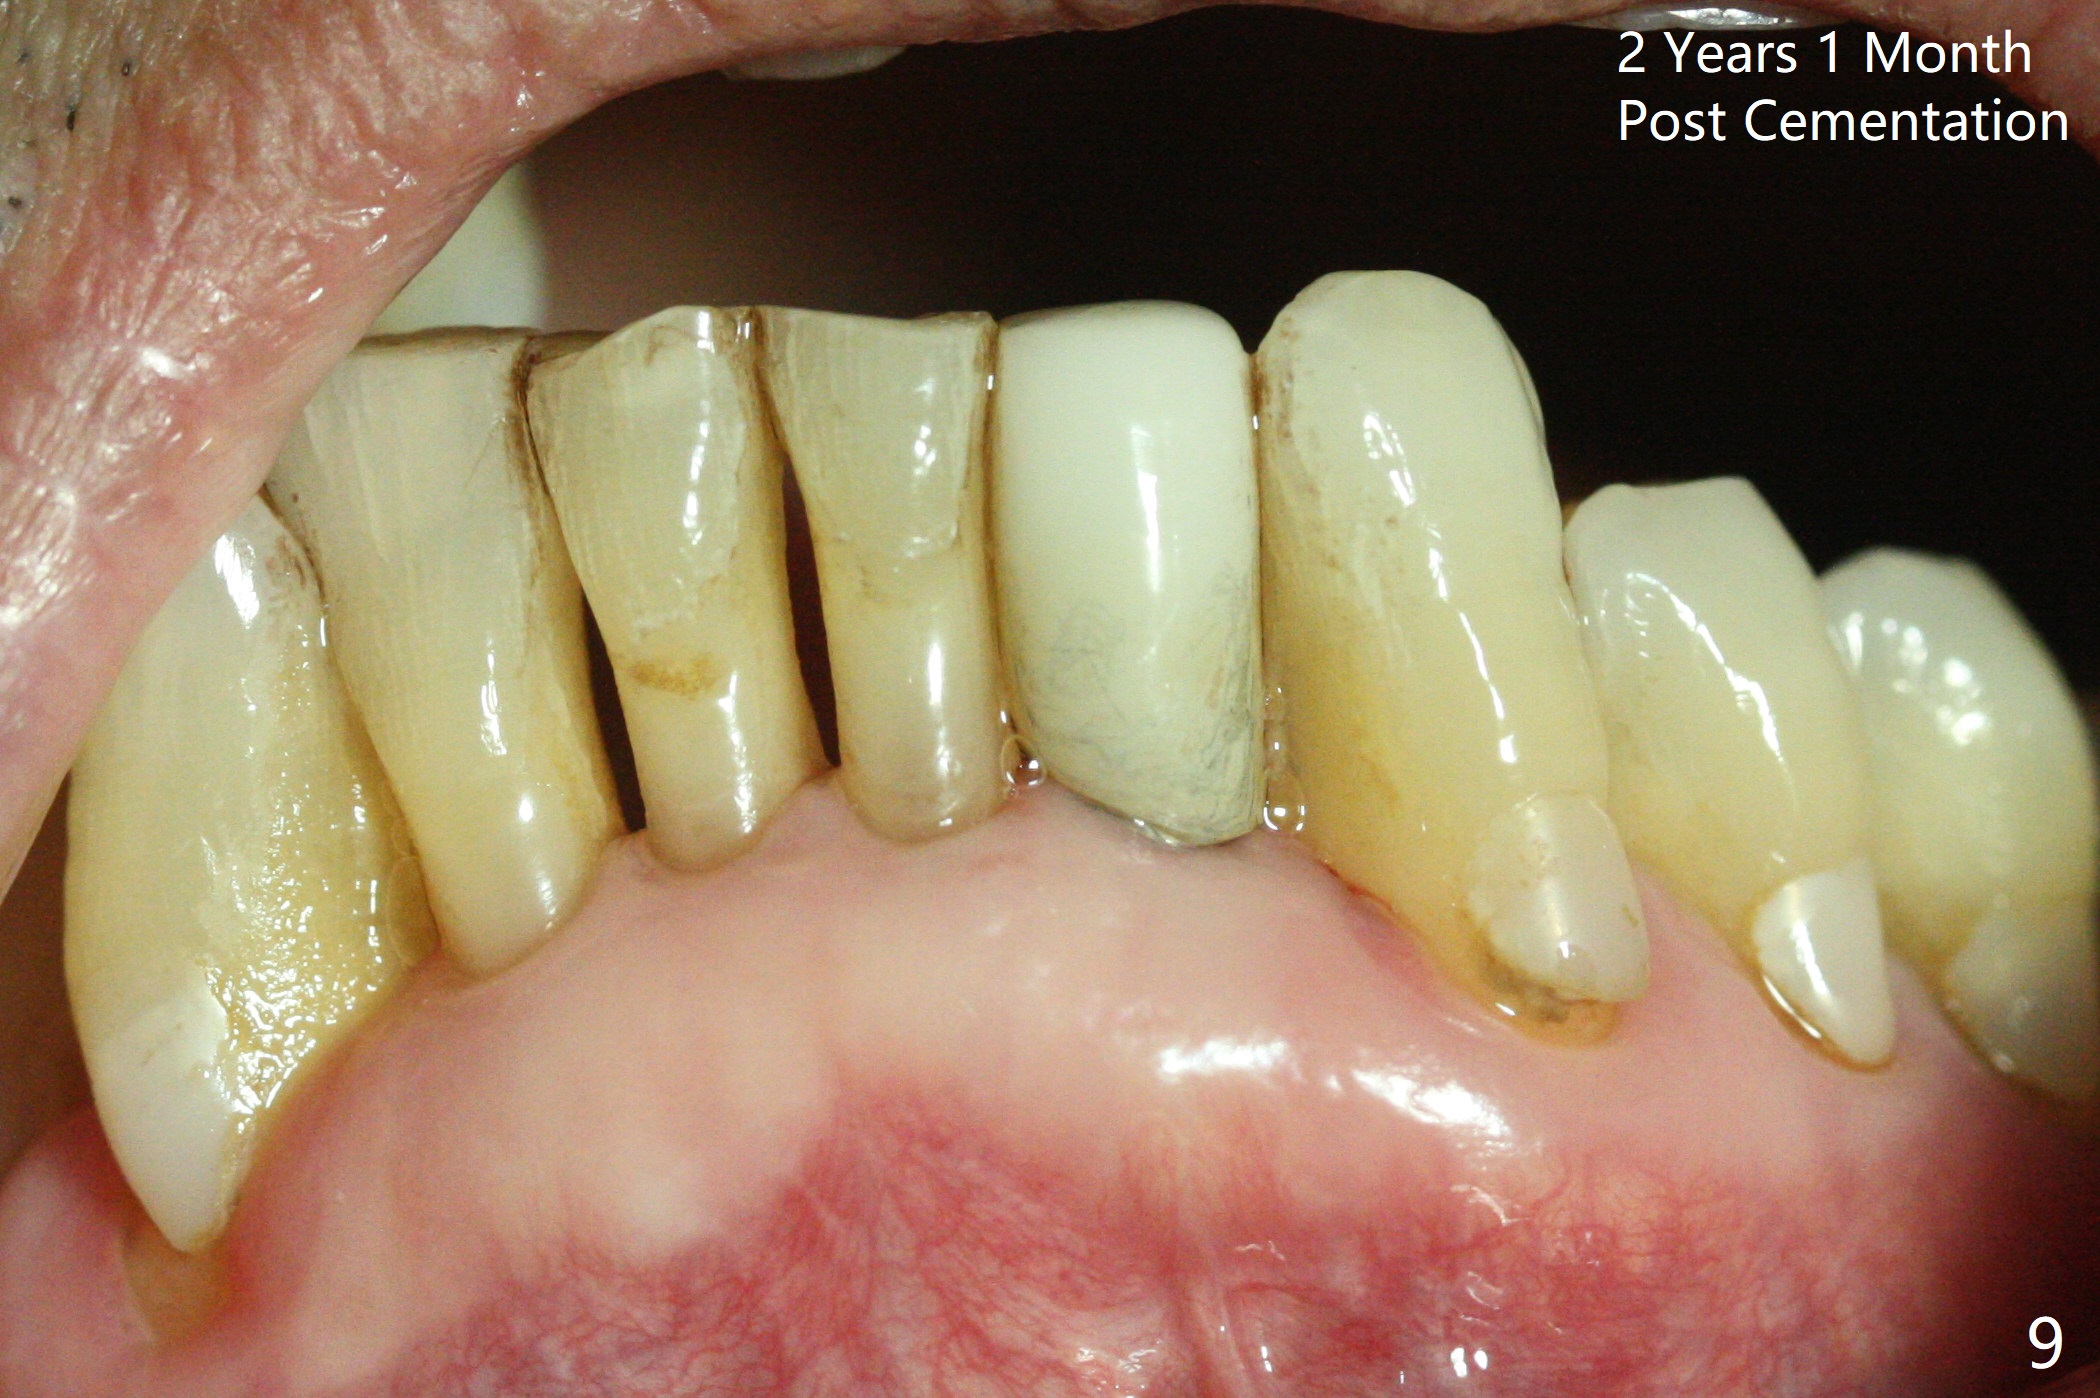

The tooth #23 is going to be extracted because the patient cannot masticate normally with mobility (Fit.1). The gingival depth is measured 2-4 mm after extraction. The 1st intraop PA taken with 1.2 mm drill for 16 mm shows the mesiodistal width is 5.11 mm (Fig.2); a 2.5x14(2) mm 1-piece implant is placed with >35 Ncm (Fig.3 with allograft placed). Following abutment preparation, an immediate provisional is fabricated to close the socket (Fig.4 P). There is no bone loss (Fig.5) or gingival inflammation (Fig.6 after reprep) 3 months postop. The narrow implant (2.5 or 2.0 mm) is indicated in the narrow edentulous space. The distal crest seems to be reduced in density and lower in height 1 year 7 months (Fig.7) and 1 year 11 months (Fig.8) post cementation. The severity does not worsen probably related to use of water pik. The crown looks bulky probably due to too large the abutment and too buccal placement of the implant (Fig.9, 10, as compared to Fig.1). A 2 mm implant may help?